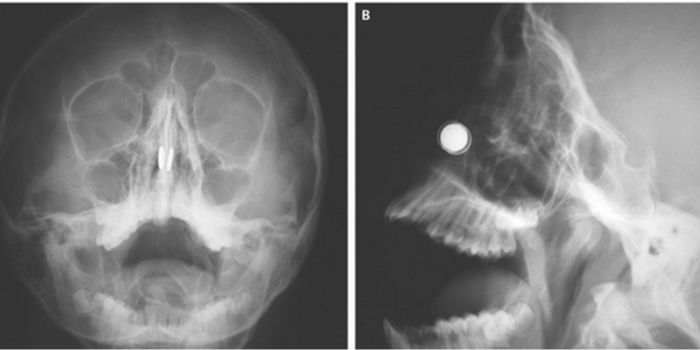

SEP 02, 2017Clinical & Molecular DXA 9-month-old infant was recently diagnosed with lead poisoning, and doctors say the source of lead came from a bracelet ...

OCT 31, 2017Clinical & Molecular DXAn 11-year-old boy recently learned a painful life lesson to never stick magnets up his nose again. Having gotten a hold ...